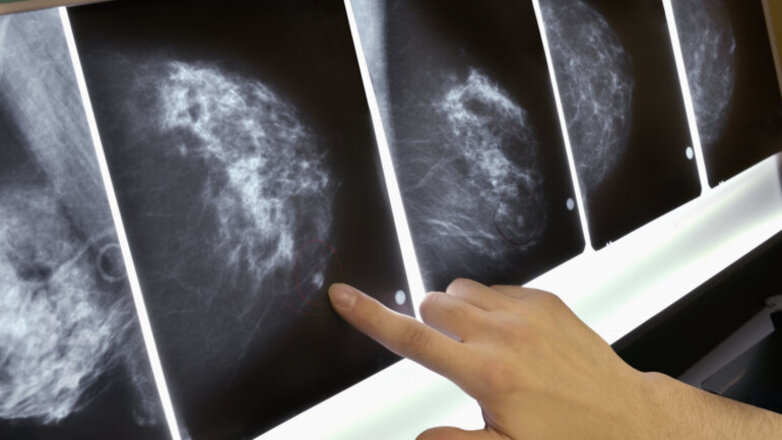

Ψηφιακή Μαστογραφία

Μέχρι σήμερα η Ψηφιακή Μαστογραφία είναι η μέθοδος εκλογής και αναφοράς για την διάγνωση του καρκίνου του μαστού, είναι δηλαδή αυτό που στη διεθνή επιστημονική ορολογία ονομάζεται ως “Gold Standard”. Όλες οι άλλες απεικονιστικές μέθοδοι είναι συμπληρωματικές.

Η Ψηφιακή Μαστογραφία, σύμφωνα με στοιχεία του Breast Cancer Surveillance Consortium των ΗΠΑ, είναι ιδιαίτερα αποτελεσματική στη διάγνωση του καρκίνου του μαστού.

Στη μαστογραφία τα ινοαδενικά στοιχεία εμφανίζονται άσπρα. Αλλά και ο καρκίνος εμφανίζεται επίσης άσπρος. Είναι επομένως πολύ πιθανό στους πυκνούς μαστούς να «χάνεται» κάποιος καρκίνος στην εικόνα της μαστογραφίας επειδή «καμουφλάρεται» από τα πυκνά ινώδη και αδενικά στοιχεία. Αναφέρεται ότι στο 1/3 των πυκνών μαστών η διάγνωση του καρκίνου μπορεί να διαφύγει της μαστογραφίας.